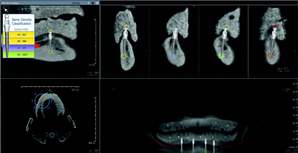

Advantages of using CBCT imaging in implant dentistry

CBCT imaging is the ideal radiological modality for implantology due to the high quality of the produced images, software capabilities, and lower doses of radiation exposure. Two of the hottest topics regarding CBCT and implantology are virtual surgery planning and surgical guides. A virtual surgery can be performed with special software applications that enable dentists to evaluate the quality of bone through density shading and dimensions of bone can be recorded accurately with 1:1 measurement tools. It identifies common internal anatomy needed to evaluate implant placement including the jaw boundaries, adjacent teeth, nasal fossa, mandibular canal, maxillary sinus, mental foramen, and incisive canal. It also detects pathology to be avoided for implant health. Therefore, before the surgery, the clinician can confirm the appropriate implant size, location and angulation, and that plan can be fed to a 3-D printer to produce a surgical guide or stent for use during the actual surgery.